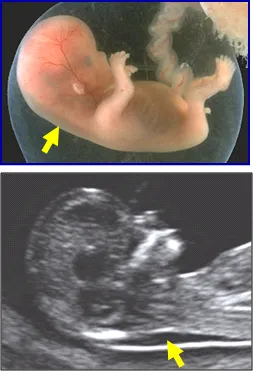

Die Auswertung zweier Substanzen im mütterlichen Blut, die nur während der Schwangerschaft gebildet werden, in Kombination mit einer Messung der kindlichen Nackenhautdichte („NT = nuchal translucency“) mittels hoch auflösender Sonographie in der 14. Schwangerschaftswoche, ist laut einhelliger Expertenmeinung die wichtigeste Ergänzung zum bestehenden altersbedingten Risiko.